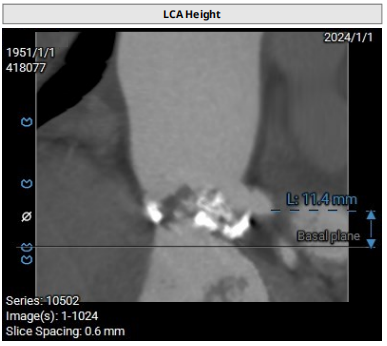

主动脉根部:Type0型二叶瓣,瓣叶钙化重,瓣环钙化,无右冠,左冠脉高度可,左冠脉开口水平可见瓣叶,左室扩张,双下肢内径可。

Type 0型二叶瓣,瓣叶钙化重,瓣环钙化,无右冠,左冠脉高度可,左冠脉开口水平可见瓣叶,左室扩张;综合评估冠脉风险低,建议球扩张进一步评估,并释放至可回收极限再次评估冠脉风险;股动脉入路可,建议右侧股动脉为主入路,二代输送系统建议20F大鞘;建议18 mm球囊预扩张,植入L26VenusA-Plus瓣膜。